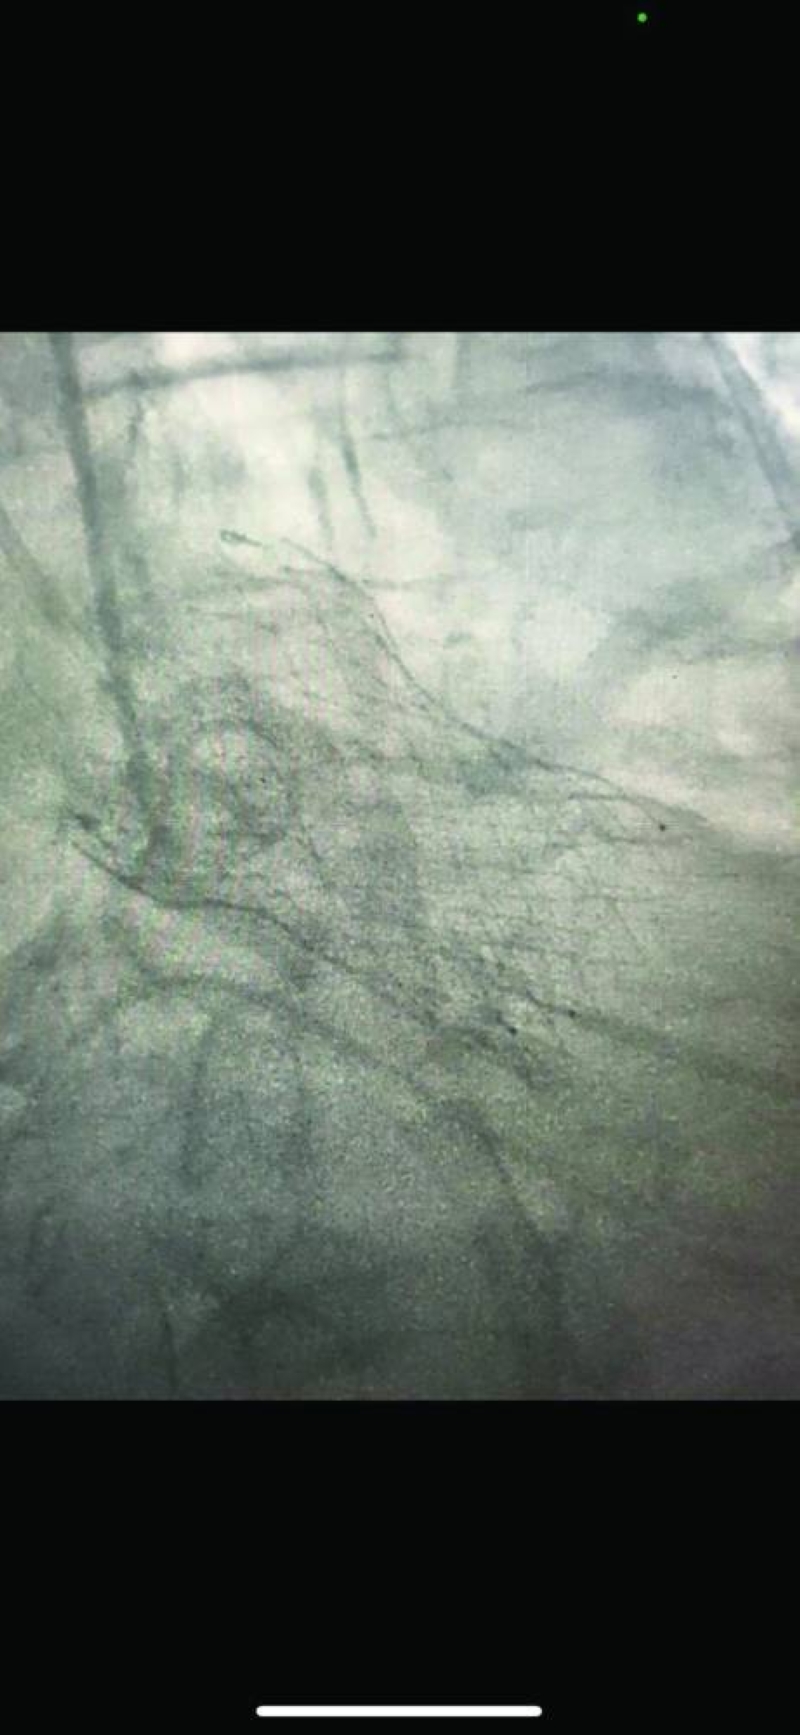

فقد نجح فريق مركز صباح الأحمد للقلب، المكون من استشاريَي القلب والقسطرة في المركز الدكتور نادر عيسى العسعوسي، والدكتور أحمد سعيد طه، في تبديل الصمام الأورطي للمريض بالقسطرة (TAVI) وتركيب دعامات بالشريان التاجي الأيسر والأيمن، فيما تمكن فريق مستشفى مبارك الكبير المكون من استشاري جراحة الأوعية الدموية الدكتور عبدالله الفواز، واستشاري الأشعة التداخلية الدكتور حسين جراغ، من إصلاح تمدد شرياني كبير بالأبهر البطني، كان على وشك الانفجار (EVAR for AAA)، وذلك في آنٍ واحد وبصفة عاجلة، وبدون جراحة لإنقاذ حياة مريض، يقارب عمره من نحو 100 عام، حيث كان المريض قد أُدخِل إلى العناية المركزة القلبية بمركز صباح الأحمد للقلب، في حالة حرجة، وهو يعاني من جلطة بالقلب وارتشاح رئوي حاد، وتجمُّع كبير للسوائل بالصدر (massive bilateral pleural effusion)، مما أدى إلى فشل تنفسي حاد. غير أن حالة المريض بعد هذا الإنجاز الطبي استقرت، وتماثل للشفاء بعد وضعه تحت العناية المكثفة، إلى أن خرج للمنزل في حالة مستقرة.

وقد تدهورت حالة المريضة على مدار سنتين، وأدخلت من الطوارئ إلى العناية المركزة للقلب بالمركز وهي تعاني من صدمة قلبية واحتشاء بعضلة القلب (acute MI and cardiogenic shock) وتجمُّع شديد للسوائل بالجسم (generalized anasarca )، حيث تم إجراء قسطرة تداخلية عاجلة، وتركيب 4 دعامات بالشريان التاجي الأيسر الرئيسي والتاجي الأيمن، تحت الدعم من المضخة القلبية الرئوية (ECMO)، وبعد ذلك تبديل الصمام الأورطي بالقسطرة (TAVI) من قبل فريق تبديل الصمام الأورطي بالقسطرة.

• تركيب 4 دعامات بالشريانين التاجي الأيسر الرئيسي والتاجي الأيمن، تحت الدعم من المضخة القلبية الرئوية (ECMO)